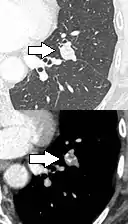

- Pleural retraction is far more common in cancers.[9] It is the pulling of visceral pleura towards the nodule.[9]

Nodule with pleural retraction.[9]

In this case, pleural retraction is seen as a triangular fat component.[9]